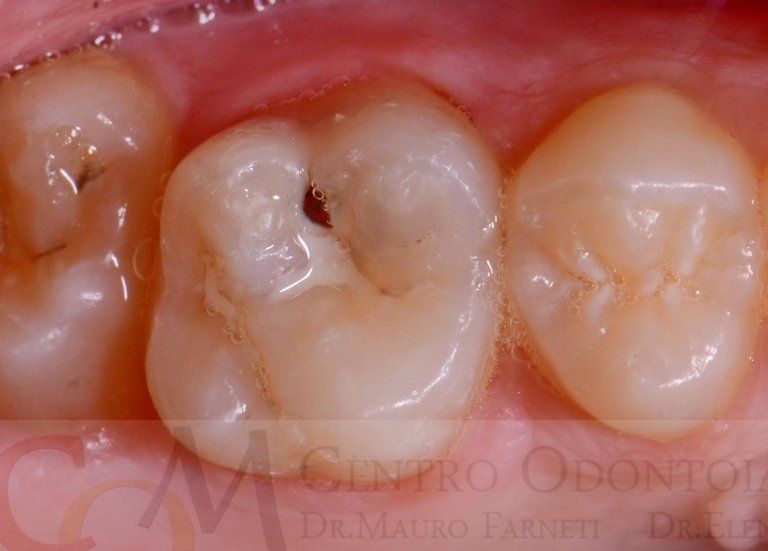

However, this practice is often carried out inconsiderately. Not all teeth need to be sealed: the morphology (i.e., shape) of the teeth, the caries susceptibility of the child, and oral hygiene at home need to be evaluated. If, based on these considerations, sealing is deemed necessary, it should be conducted according to a precise clinical protocol, which includes the application of a rubber dam (see topic in "Services"), cleaning of any pigmented grooves, and bonding of the sealant. "Forgetting" one of these steps results in poor-quality therapy: for example, sealing grooves without prior cleaning risks sealing decay underneath. Upon inspection by the dentist, these grooves would appear sealed... but so would the underlying decay, which wasn't removed, making it invisible. This would result in dental decay that cannot be diagnosed in its early stages as it is "covered" by the dental sealant... truly not a good job! Below are examples of correctly sealed and emblematic cases of how sealing should NOT be performed.